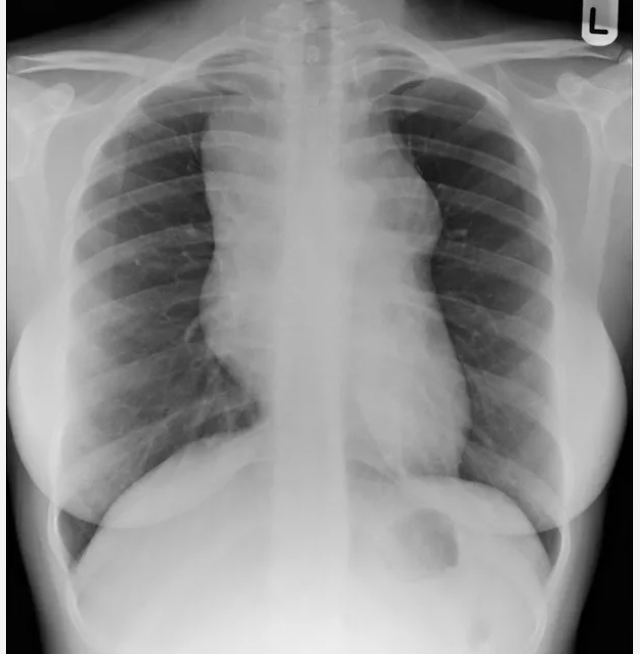

이후 흉부 X-ray 를 촬영하여 경부 림프절 종대 환자에서 종격동 림프절 비대를 확인하는데,

이경우 호즈킨 림프종(HL) 가능성이 커집니다.